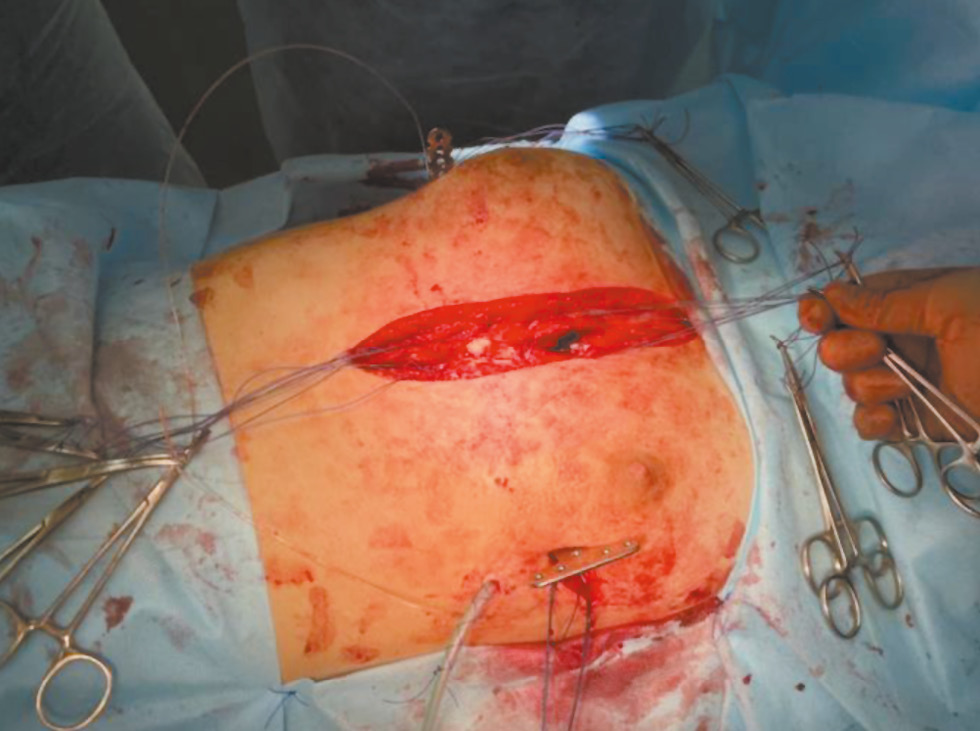

Всего по методу Насса с использованием ВК прооперированы 15 пациентов. Из них 13 мальчиков и 2 девочки в возрасте от 8 до 17 лет (средний возраст 15,0±2,6 лет). Показаниями к интраоперационной элевации грудины являлись глубокие ВДГК (индекс Галлера более 4,5 см) (рис. 1), вариант деформации «Grand Canyon» и ВДГК после стернотомии (рис. 2). Также ВК использовался в качестве предоперационной подготовки у 5 пациентов (табл. 1).

Рис. 1. Пациент 16 лет: a — воронкообразная деформация грудной клетки; b — компьютерная томография грудной клетки (индекс Галлера =5,4 см).

Предоперационное обследование пациентов, у которых использовался ВК при выполнении торакопластики по Нассу, не отличалось от обследования остальных пациентов с ВДГК и включало общеклинические анализы, рентгенографию грудной клетки, эхокардиографию, эзофагогастродуоденоскопию, консультацию генетика и, в случаях сложных анатомических вариантов, компьютерную томографию грудной клетки.